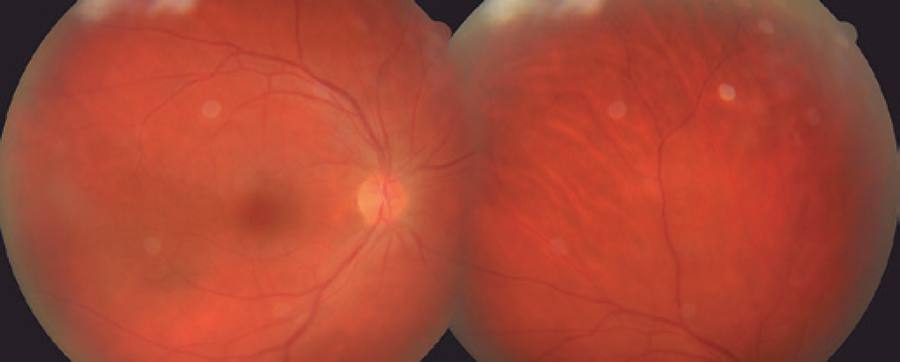

A 44-year-old male patient presented to our clinic with symptoms of floaters in both eyes for a week. The best corrected visual acuity (BCVA) was 0.8 on the right eye and 0.9 on the left, and intraocular pressures were normal. The case had been followed up for mucosal LP for the last 10 years at another center. Anterior segment examination was normal for both eyes. Bilateral intensive vitritis and peripheral vascular sheathing were observed on fundus examination (Figure 1). FA investigation revealed staining and leakage of the mid-peripheral vessels in the early stage and of the optic disc and surrounding vessels in the late stage (Figure 2). The patient had no history of urogenital or oral ulceration, skin rash, weight loss, cough, night sweats, lymphadenopathy, arthritis, arthralgia, neurological symptoms, gastrointestinal symptoms, travel to foreign territories, or contact with animals. No evidence of pathology was found in tests performed to investigate the etiology of retinal vasculitis, and complete blood count, biochemical tests (glucose, urea, creatinine, electrolytes, and liver and kidney function tests), erythrocyte sedimentation, C-reactive protein, FTA-ABS, VDRL, Lyme IgM and IgG, HIV serology, urine analysis, rheumatoid factor (RF), anti-neutrophil antibody (ANA), tuberculin skin test (PPD), and chest X-ray tests were all normal. The results of cranial and orbital magnetic resonance imaging were normal. Consultations with various departments were performed to exclude Behcet's disease, sarcoidosis, systemic lupus erythematosus, multiple sclerosis, and tuberculosis, some of the most common etiologic causes of retinal vasculitis. Because of suspected LP, fluocortolone tab (1 mg/kg), cyclosporine tab (2 x 100 mg), and azathioprine tab (2 x 50 mg) were started as systemic treatment. No topical treatment was used. Corticosteroid treatment was gradually decreased and eventually stopped. BCVA fully recovered bilaterally at the first month of follow-up, and the vitritis and peripheral vascular sheathing had regressed. BCVA and anterior and posterior segment examinations were normal within the first year follow-up; therefore, the immunosuppressive treatment was discontinued (Figure 3).

Figure 1 Color fundus photography showing mid-peripheral vascular sheathing. Images appear blurred because of intensive vitritis.